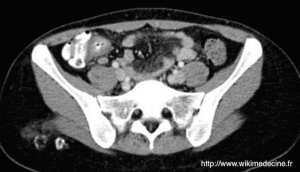

- Echographie ou CT-scanner abdominal :

- Confirme la présence d'adénopathies mésentériques supracentimétriques (ou des clusters d'au moins 3 adénopathies de plus de 5 mm de grand axe), peut mettre en évidence un épaississement de la paroi grêle ou colique en regard, estime la sévérité et d'éventuelles complications et permet d'éliminer les diagnostics différentiels chirurgicaux (l'appendice doit être normal)